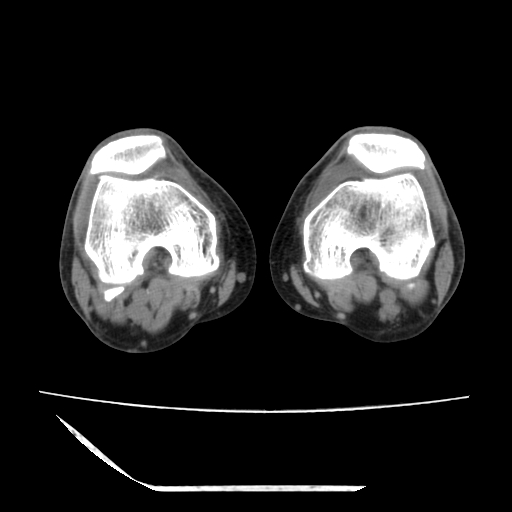

标题: CT13225:老年男性,左膝关节疼痛数月;请各位老师讨论。 [打印本页]

标题: CT13225:老年男性,左膝关节疼痛数月;请各位老师讨论。

骨质增生,骨性关节面硬化,关节积液,考虑退行性骨关节病

关节腔内少量积液,关节面退变。

双膝退变

骨质增生,骨性关节面硬化,关节间隙失常,关节积液,考虑退行性骨关节病.

骨质增生,骨性关节面硬化,关节积液,考虑退行性骨关节病。

这个病例诊断:退行性骨关节炎